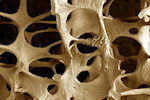

Η οστεοπόρωση είναι νόσος που οφείλεται στην απώλεια οστικής μάζας. Η οστική μάζα σχηματίζεται σιγά - σιγά από την αρχή της ζωής του ανθρώπου, φθάνει στη μεγαλύτερη πυκνότητα της (κορυφαία οστική μάζα) στην ηλικία των 25-35 ετών και από την ηλικία των 45 ετών αρχίζει να μειώνεται σταδιακά.

Στην οστεοπόρωση, η σύνθεση του οστού και ο όγκος του σκελετού παραμένουν φυσιολογικά ενώ η οστική μάζα ελαττώνεται και μ' αυτό τον τρόπο τα οστά γίνονται «αραιότερα», με μειωμένη αντοχή και μεγαλύτερη πιθανότητα να πάθουν κατάγματα όταν ασκούνται πάνω τους δυνάμεις. Όσο μεγαλύτερη οστική μάζα έχει ο άνθρωπος τόσο μειώνει τον κίνδυνο να πάθει οστεοπόρωση. Αυτή η διαπίστωση αποτελεί το «κλειδί» στην πρόληψη της νόσου.